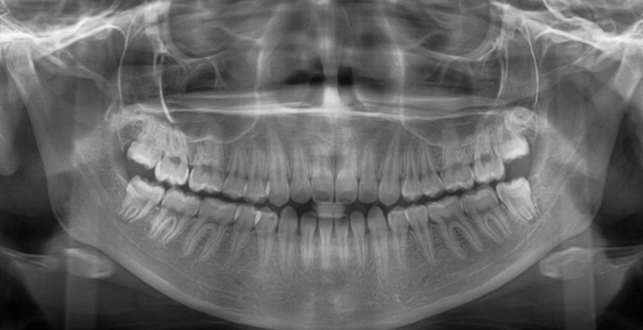

| 年齢・性別 | 15歳の女性 |

|---|---|

| 主訴 | 咬み合わせが逆であること(反対咬合)を気にされて来院された15歳7か月の女性。見た目や機能面の改善を希望されていました。 |

| 治療期間・回数 | 4年4ヶ月・28回 |

| 費用 | 900,000円 |